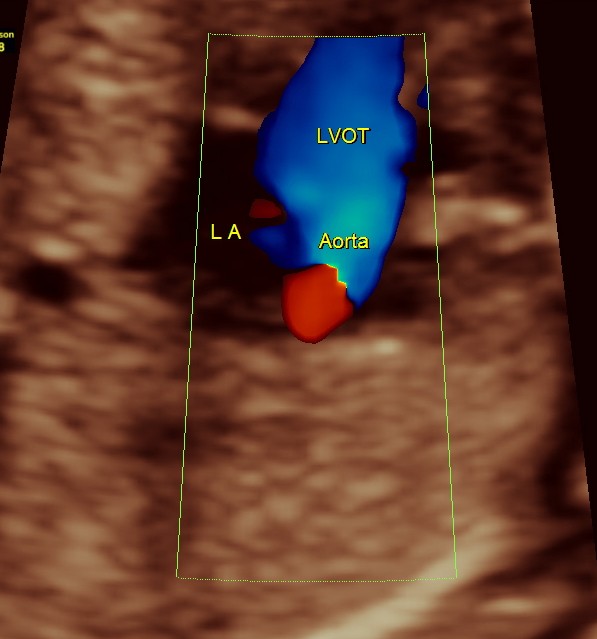

The following pictures are of the 20 weeks gestation.

The following are of the 26 weeks gestation.

The following are of the 34 weeks gestation :

The following are from the 37 weeks scan.